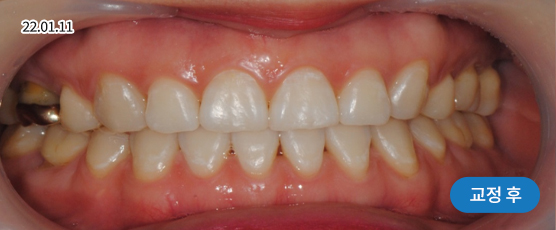

* 본 사진은 동일 조건에서 촬영되었으며, 환자 본인의 동의를 얻어 게재되었습니다.